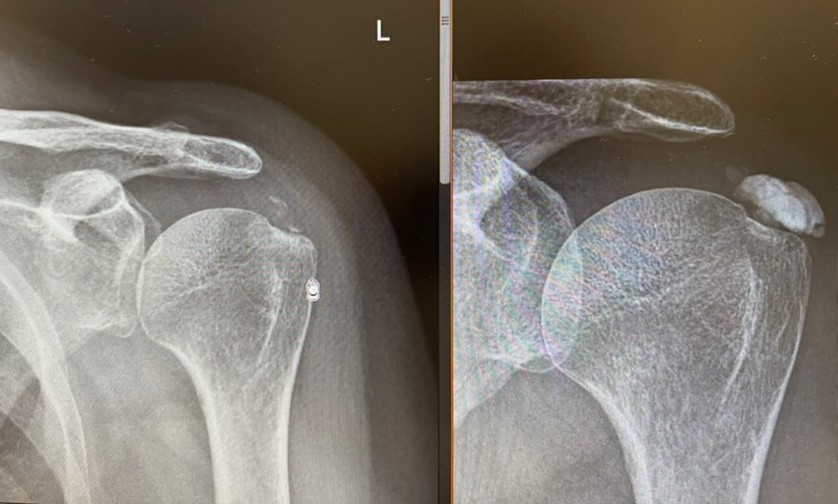

El antes y el después:

El lavado ecoguiado de calcificación es una técnica mínimamente invasiva destinada a tratar la tendinitis calcificada del hombro u otras localizaciones. Consiste en introducir una fina aguja guiada por ecografía hasta la calcificación y realizar un lavado con suero para fragmentarla y extraerla parcialmente. El objetivo es reducir la presión dentro del tendón y disminuir la inflamación. Es una alternativa eficaz cuando el dolor limita el movimiento o persiste pese a otros tratamientos.

• Calcificaciones visibles en ecografía que producen dolor mecánico o inflamatorio.

La mejoría suele ser mantenida. En muchos casos el procedimiento no necesita repetirse. Si queda calcificación residual y persiste el dolor, puede considerarse un segundo lavado o completar con fisioterapia específica.